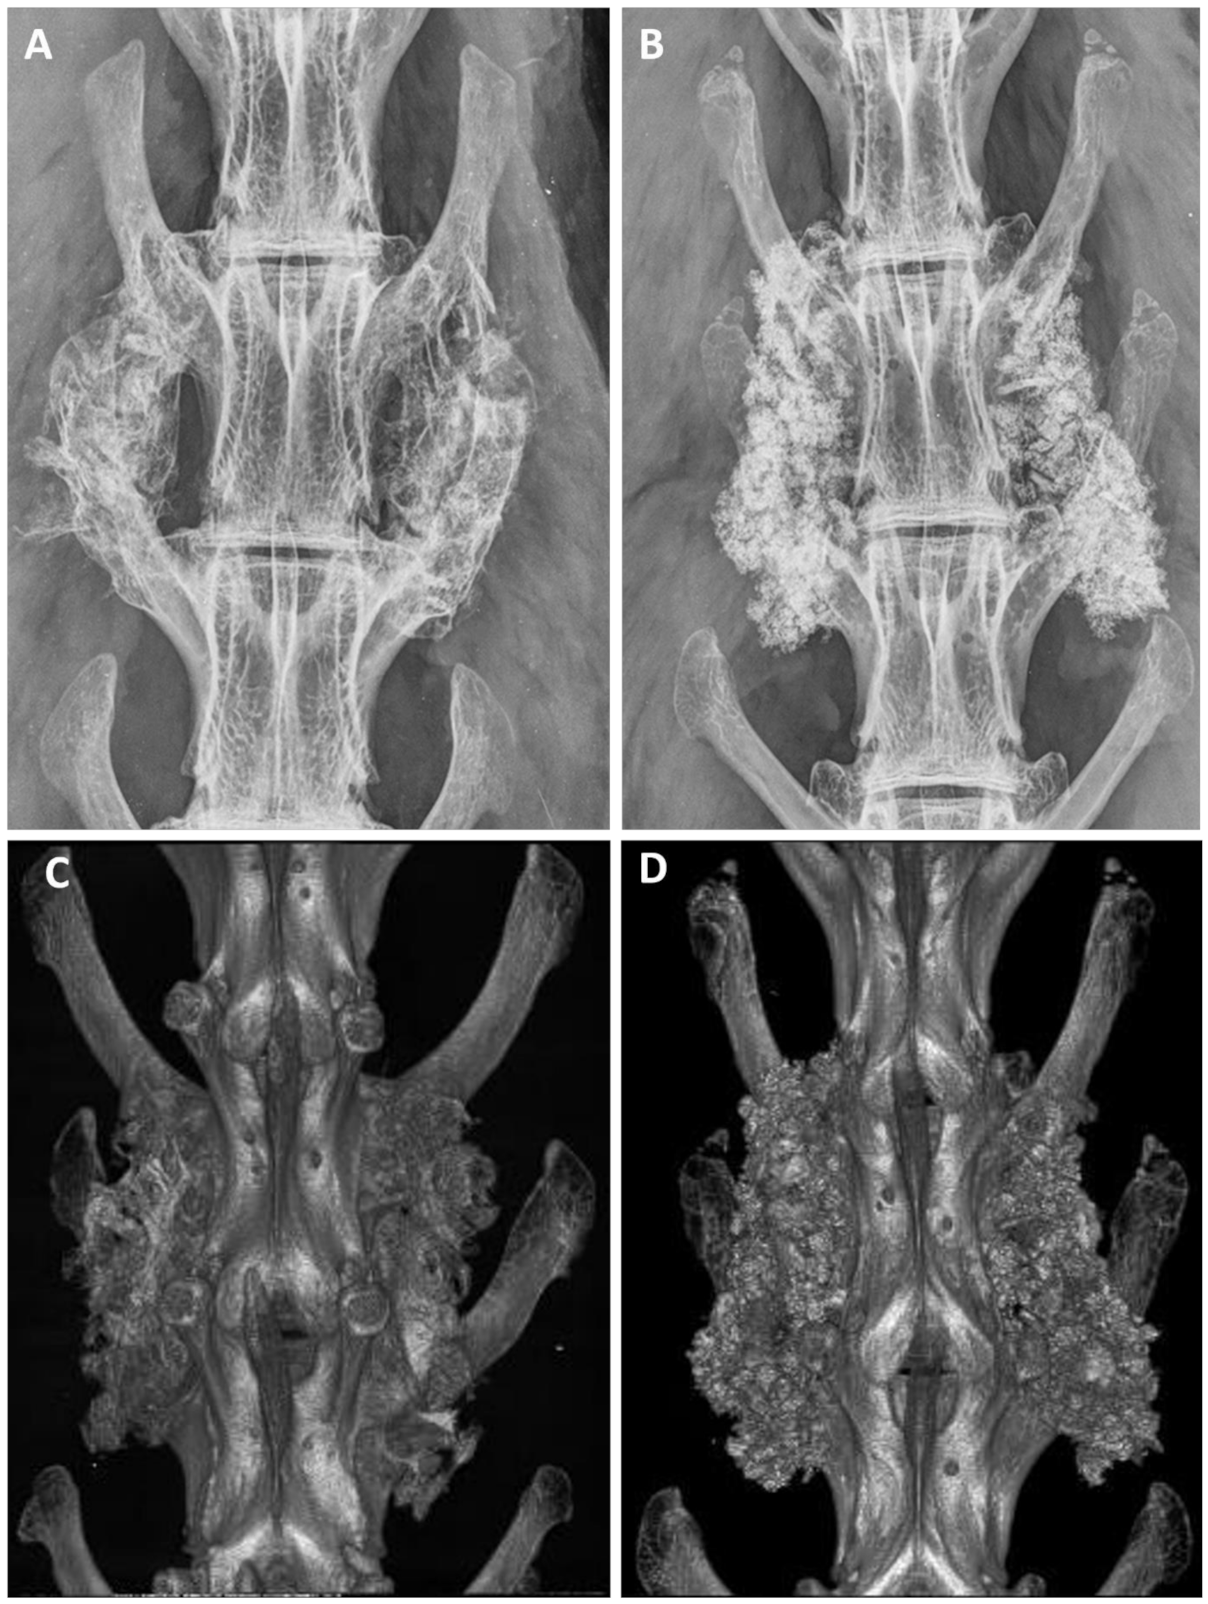

After euthanasia, anteroposterior radiographs were analyzed to evaluate the implantation. The analysis by radiography and micro-CT revealed successful implantation in all animals, and no adverse bony reactions or graft migration (Figure 4). The grading distribution according to the Lenke scale was comparable between ABG and BCP-EP/ABG with no statistical difference. A high occurrence of Grade A was observed at 12 weeks for both groups through radiographic analysis and micro-CT scans, indicating the presence of a solid bilateral fusion at this timepoint. The fusion rates were 62.5% and 75% for BCP-EP/ABG and ABG, respectively, according to both radiographic and micro-CT analysis.

Figure 4.

Representative examples of Faxitron radiographs taken after 12 weeks for (A) ABG and (B) BCP-EP/ABG. Representative examples of 3D micro-CT reconstructions taken after 12 weeks for (C) ABG and (D) BCP-EP/ABG. The Faxitron radiographs and micro-CT reconstructions show the presence of graft material bridging the intertransverse process space of the treated levels in all groups.